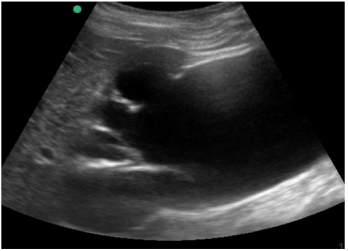

Um paciente de 72 anos de idade foi para a Unidade de Terapia Intensiva (UTI). Institucionalizado, com duas internações nos últimos seis meses por conta de sepse de foco urinário. Na admissão, realizou ultrassonografia abdominal com o achado demonstrado na imagem apresentada. Os exames laboratoriais mostraram ureia = 230, creatina = 10 e potássio = 7,5.